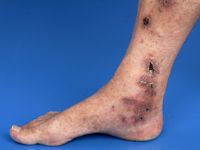

| leukocytoclastische vasculitis | leukocytoclastische vasculitis | leukocytoclastische vasculitis |